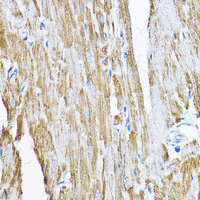

Immunohistochemical analysis of Sam50 staining in rat heart formalin fixed paraffin embedded tissue section. The section was pre-treated using heat mediated antigen retrieval with sodium citrate buffer (pH 6.0). The section was then incubated with the antibody at room temperature and detected using an HRP conjugated compact polymer system. DAB was used as the chromogen. The section was then counterstained with haematoxylin and mounted with DPX.